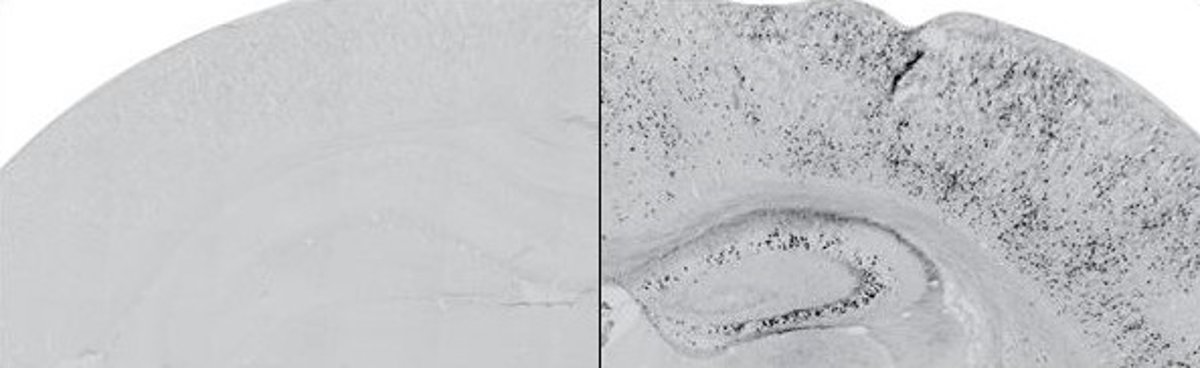

Acumulación experimental del fragmento de la proteína neurexina en el modelo animal (en negro, panel derecho), respecto a ratones control (panel izquierdo)

Acumulación experimental del fragmento de la proteína neurexina en el modelo animal (en negro, panel derecho), respecto a ratones control (panel izquierdo) - UNIVERSIDAD PABLO DE OLAVIDE

Los investigadores se han centrado en el estudio de un fragmento de la proteína sináptica neurexina, denominada en el ámbito científico como NrxnCTF. Este fragmento se acumula en los casos de mutación en los genes de presenilinas responsables de formas familiares de Alzheimer.

Los expertos han observado que su acumulación experimental en el cerebro adulto del modelo animal desencadena defectos específicos de memoria, entre otros. Estos modelos experimentales de enfermedad son importantes para la identificación de mecanismos patogénicos y fundamentales para el diseño de terapias efectivas.